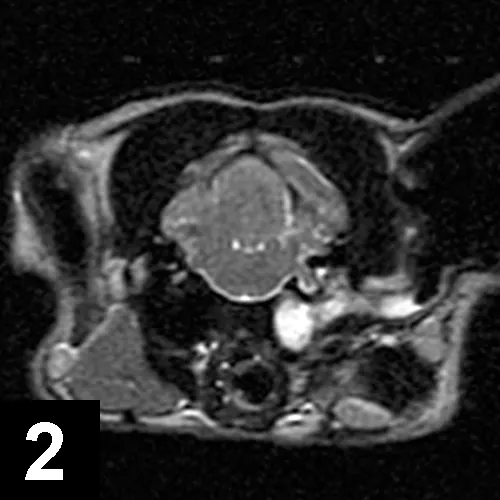

FIGURE 2

Axial T2-weighted MRI of a cat with left-sided Horner syndrome and peripheral vestibular dysfunction secondary to severe otitis.